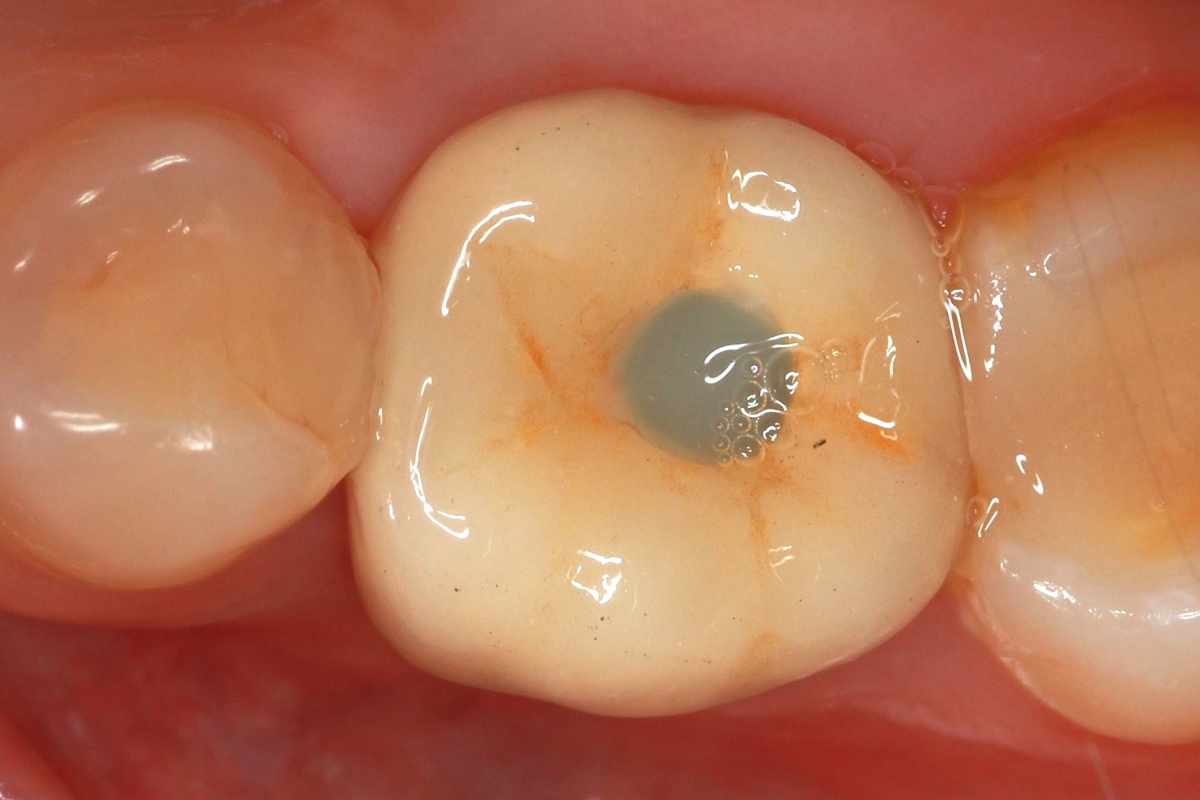

Installing the crown

We install an individual abutment, fix the crown